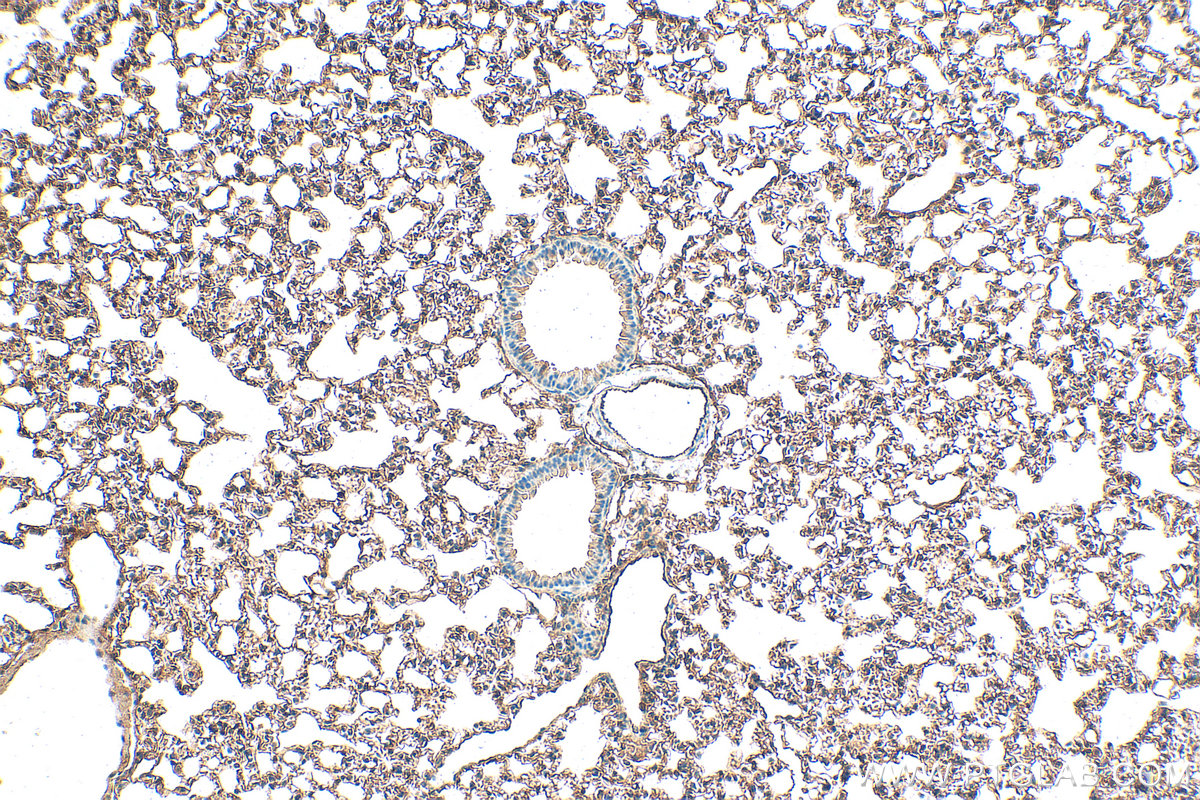

| Positive IHC detected in | human lung tissue, human brain tissue, mouse brain tissue, mouse lung tissue Note: suggested antigen retrieval with TE buffer pH 9.0; (*) Alternatively, antigen retrieval may be performed with citrate buffer pH 6.0 |

| Immunohistochemistry (IHC) | IHC : 1:50-1:500 |